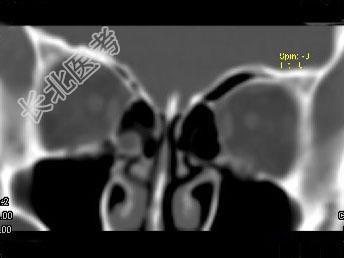

- 单项选择题女,25岁, 因眼部外伤来院就诊,CT如图所示, 最可能的诊断是 ( )

A、右侧颧弓骨折伴筛窦积血

B、右眼眶内侧壁骨折伴筛窦积血

C、右眼眶外侧壁骨折伴筛窦积血

D、右眼眶内外侧壁骨折伴筛窦积血

E、蝶骨骨折伴筛窦积血